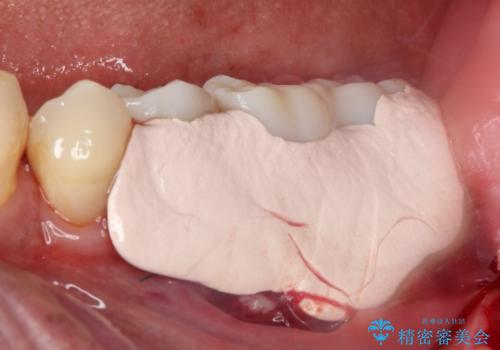

インプラント埋入後、手前のインプラント周りの丈夫な歯肉(角化歯肉)が失われてしまったため、角化歯肉の移植を行うこととなりました。

十分な角化歯肉が獲得でき、清掃性の高い環境が達成されました。